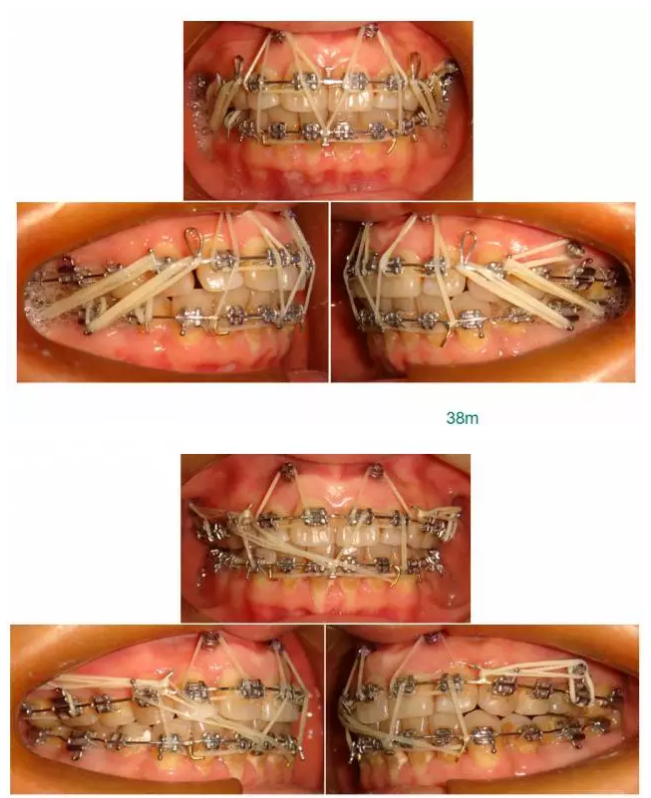

【原創(chuàng)博客】這樣的代償矯治大家滿意嗎?(重度骨性二類)——侯志明

QQ圖片20150824150559.png

QQ圖片20150824150613.png